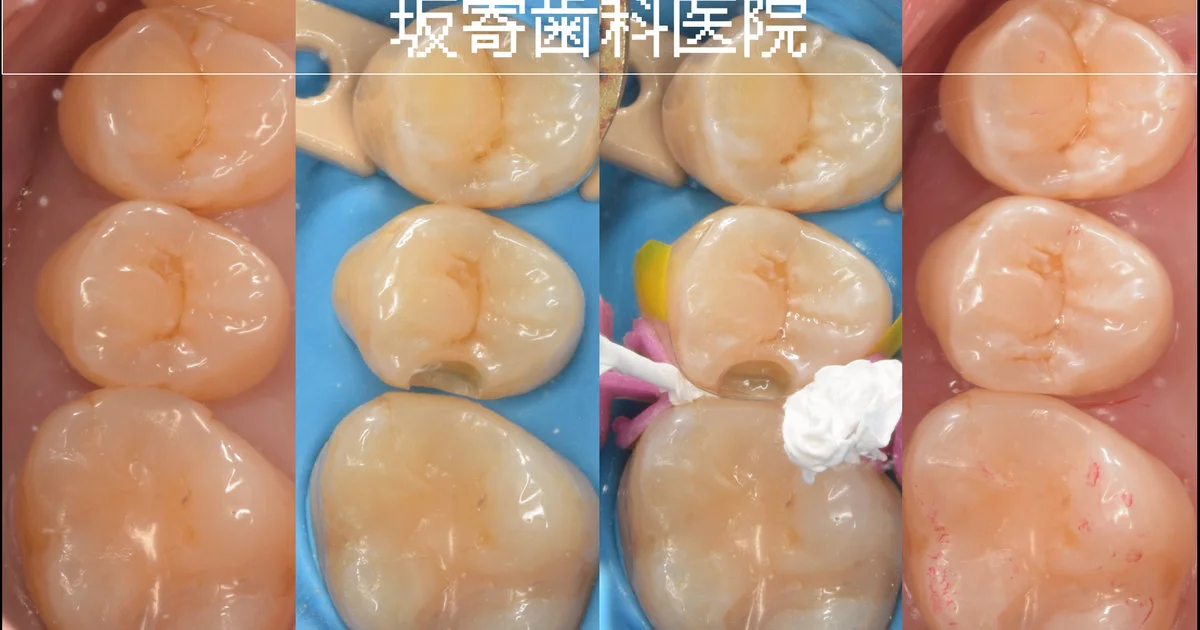

歯質を温存しながら左上の臼歯3本をダイレクトボンディングで修復

東京都内からお越しの30代女性(歯科医師)の患者さんです。経過観察していた左上5番 近心のむし歯が象牙質の半ば(1/2程度)まで進行したため、左上4・5・6番の3本を同日にダイレクトボンディングで修復した症例です。健康な歯質を最大限温存することを優先し、ラバーダム防湿下で精密に接着処理を行いました。